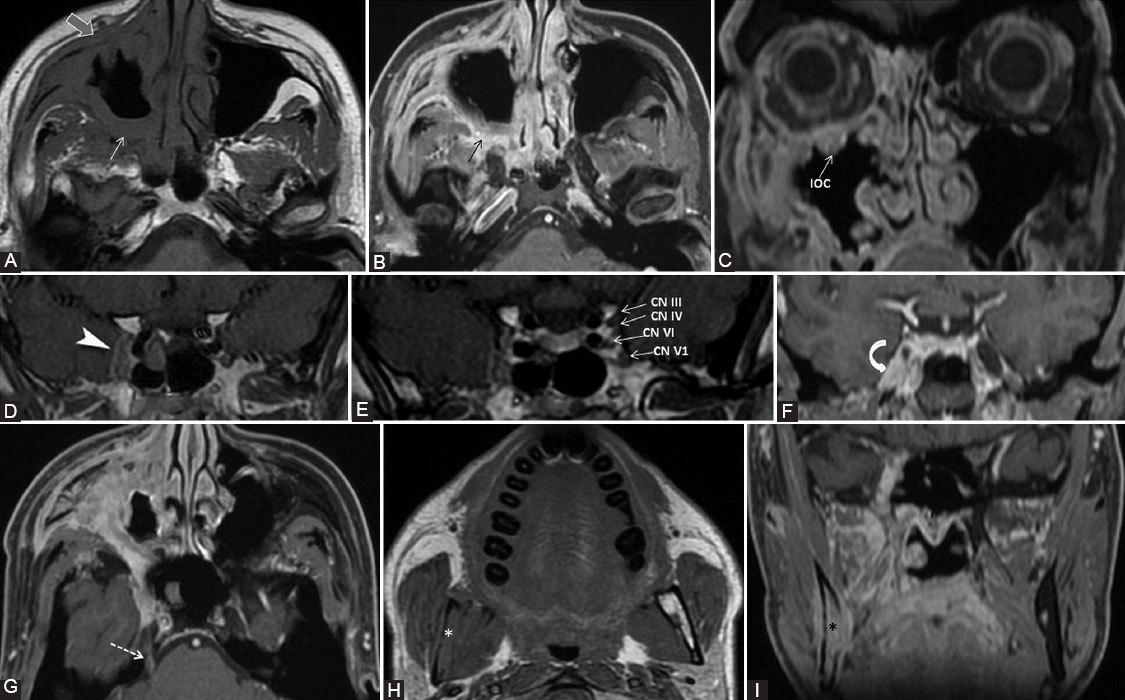

Perineural spread (PNS) represents the tumor’s ability to disseminate along nerves. The aim of this article is to review the relevant literature about the PNS in head and neck tumors (HN). The important information for imaging analysis is summarized in a diagnostic flow-chart. The pathogenesis, clinical signs, prognostic importance, and technical considerations for computer tomography and magnetic resonance imaging are briefly discussed. The anatomical pathways of the cranial nerves (CNs) and the main check-points are synthesized. Most commonly affected nerves are the trigeminal and facial, although any of the CNs may be involved. The described imaging features represent important clues for an optimal differential diagnosis. PNS worsens the prognosis and significantly changes the treatment, thus radiologists should be aware of this entity and be able to find it on imaging in the appropriate clinical context.